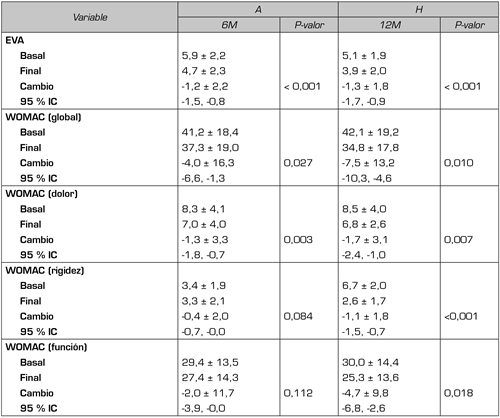

No hubo distinciones significativas entre los dos grupos con respecto a la demografía o a los valores basales de los cuestionarios de referencia (Tabla II), con la salvedad de la EVA que mostraba una diferencia de 0,8 puntos con una p = 0,015. No obstante, dado que de manera estandarizada se considera que en la medición del dolor con la escala EVA, debe producirse un cambio de al menos dos puntos para considerarse significativo, esta diferencia tiene un valor relativo. Los resultados intragrupo en relación con la evolución de los pacientes desde el inicio del tratamiento se muestran en la Tabla III. Se observa que el grupo A6M, que recibió una infiltración con A y volvió a la consulta 6 meses después, mostró mejoras significativas en relación con la disminución del dolor en la cadera medida tanto con la EVA (p < 0,001) como con el WOMAC dolor (p = 0,003), así como en el resultado del índice WOMAC global (p = 0,027). Sin embargo, no se produjeron cambios estadísticamente relevantes en el apartado de la rigidez y de la función medidos con el WOMAC. En lo que se refiere al grupo H12M, evaluado al año de la infiltración mostró mejora significativa en todos los parámetros registrados. Tanto la EVA (p < 0,001) como el WOMAC global (p = 0,010) y sus diferentes dimensiones registraron mejorías significativas. Es relevante el resultado del valor WOMAC rigidez que a los 12 meses mostró una mejora significativa importante (p < 0,001) y en menor medida el WOMAC función (p = 0,018).

Tabla III: Pacientes tratados con A a los 6 meses o H a los 12 meses. Significación de los cambios

de las medias intragrupos.

EVA: escala analógica visual. WOMAC: Western Ontario and McMaster Universities Ostearthritis Index. Datos proporcionados como media + DS (desviación estándar). IC: Intervalo de confianza. Ns: no significativo. Fue usado el test Wilcoxon para evaluar los resultados con un valor alfa establecido en 0,05 como significativo.

En la Figura 3 se muestra la comparativa de los cambios obtenidos en cada grupo después del tratamiento con AH. En relación con el dolor medido utilizando la escala EVA y con el WOMAC dolor se observa que la reducción se mantiene en ambos grupos, pero sin diferencias estadísticamente significativas (p > 0,05). Por el contrario, los cambios en los índices de WOMAC función, WOMAC rigidez y WOMAC global fueron superiores en el grupo H12M comparado con el grupo A6M (p = 0,040; p = 0,003, p = 0,043, respectivamente).